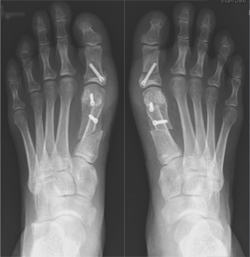

• Surgical Technique – Scarf and Akin Osteotomy

This is the most common procedure used to correct bunions in the UK and Europe. It is also the technique that I use for the majority of my patients.

It involves removing the prominent bump and realigning the metatarsal bone with an osteotomy (cut in the bone followed by screw fixation), combined with repair of the joint capsule and ligaments. This will produce a narrower foot and a straighter big toe. There may also be simultaneous surgery on the lesser toes, if needed.

The term 'Scarf' is a joinery term, and describes the 'Z' shaped cut that I use in this operation in order to straighten the big toe.

Following making a skin incision over the inner aspect of the foot, the first metatarsal bone is cut in a Z fashion, and the metatarsal is shifted into the correct position. This new position is held with small titanium screws. A second cut is often needed in the first bone of the big toe as well, and this is called an 'Akin' osteotomy. It corrects the deformity fully and is fixed with the same small screws.

Image of x-ray showing feet with bunion  Image of x-ray showing feet with bunion corrected using screw fixation